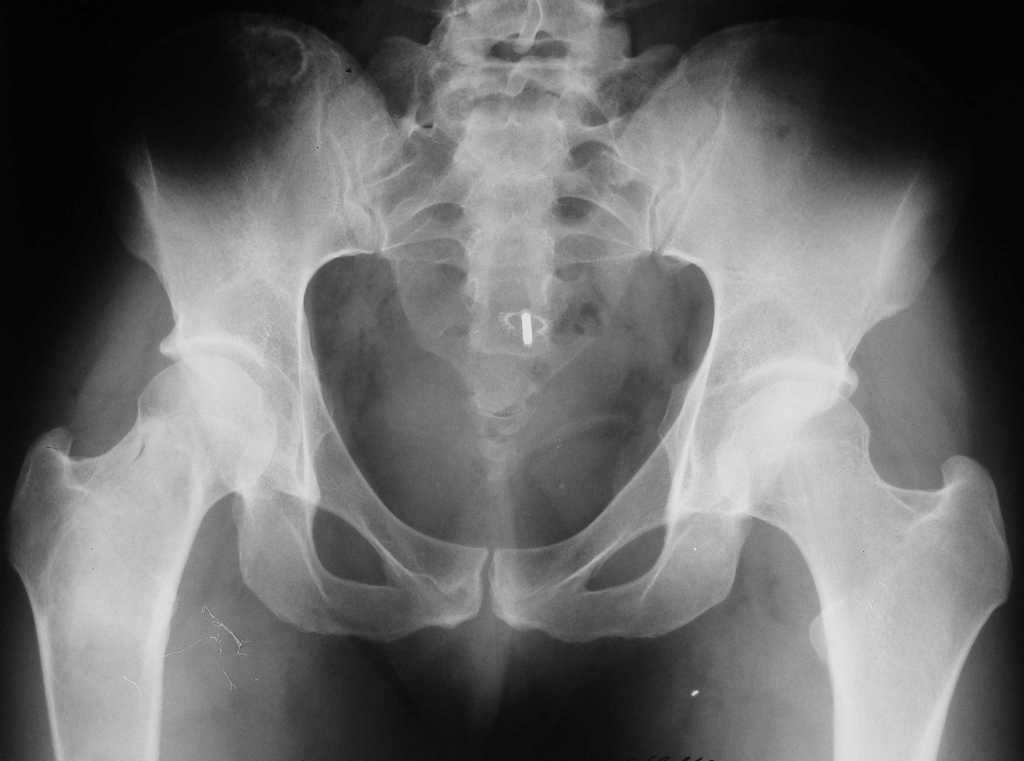

Уважаемые коллеги! В клинику поступила молодая женщина 35 лет с жалобами на интенсивные боли в области правого бедра, носят спонтанный характер, имеются "ночные" боли.

Движения в правом тазобедренном суставе в полном объёме, практически безболезненные. По результатамx-ray диагностики выявлен патологический очаг, занимающий весь проксимальный отдел и 2/3 диафиза правой бедренной кости. Другие трубчатые кости верхних и нижних конечностей - без очагов поражения.

Имеется небольшой (1,5х2,5 см) очаг в крыле правой подвздошной кости.

К тому же на снимке виден на мой взгляд обширный литический очаг в средней и верхней трети бедренной кости центрального расположения с не четкими границами с утоньшением кортекса и периостальной реакцией вверхней трети латерально.